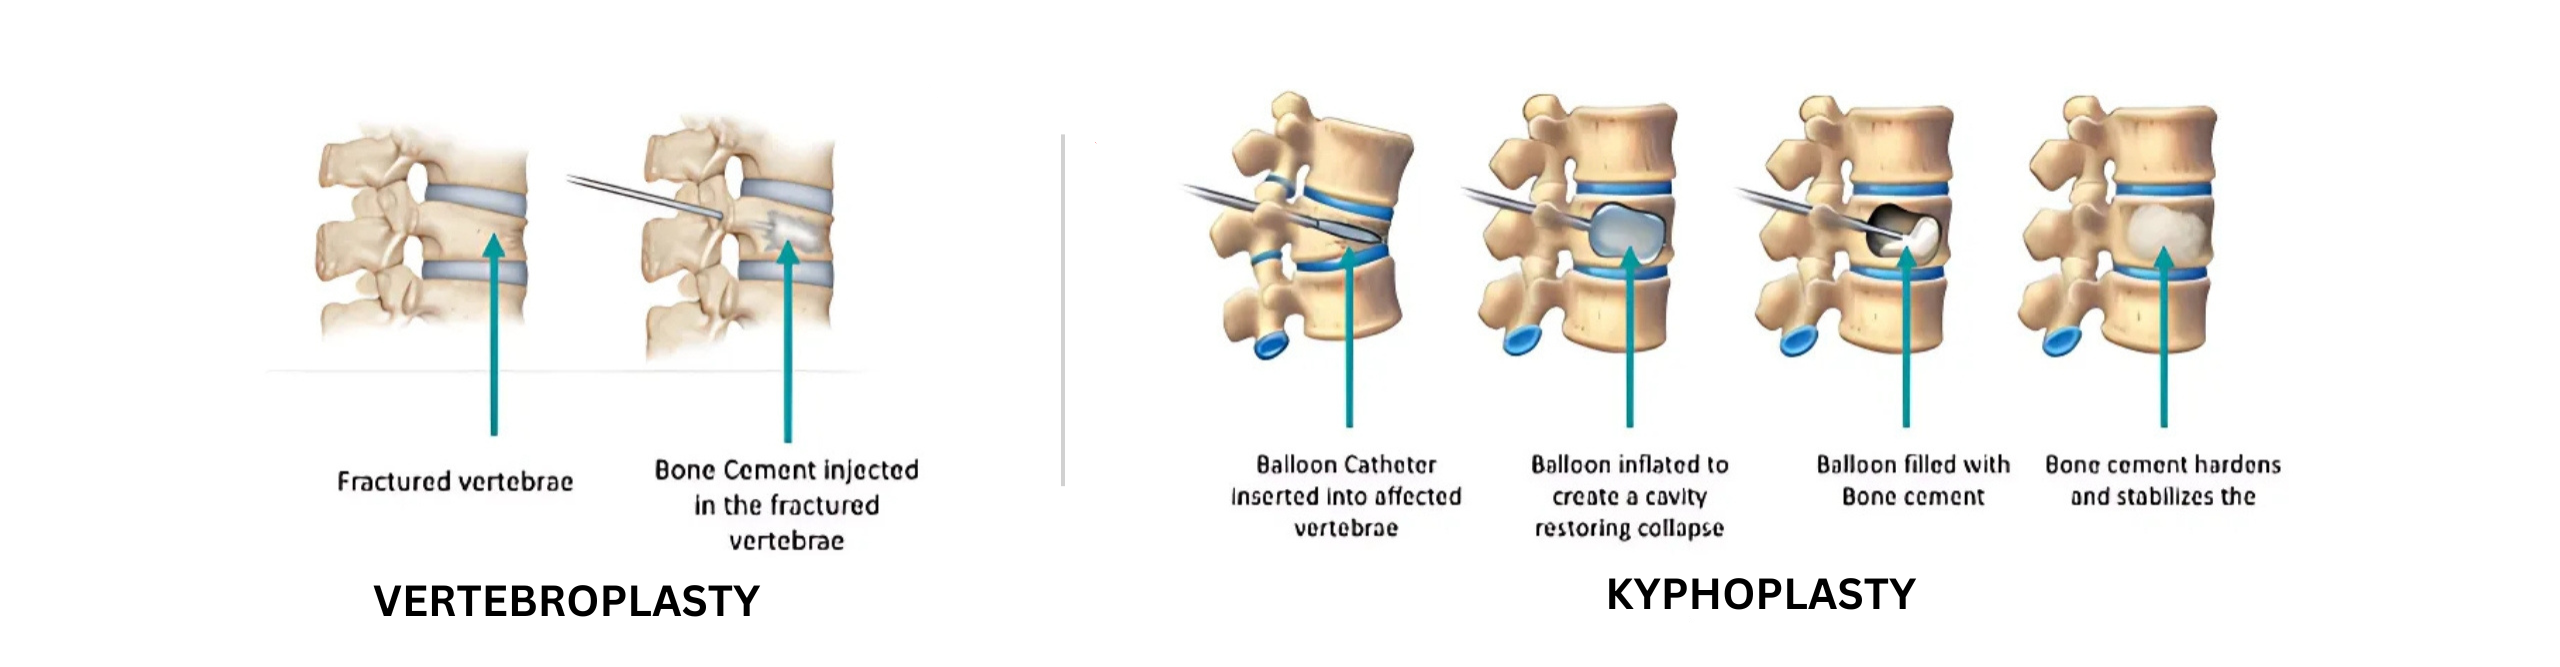

Vertebroplasty and kyphoplasty are both minimally invasive procedures performed under fluoroscopic guidance to treat vertebral compression fractures. These fractures typically occur in the thoracic (mid-back) or lumbar (lower back) regions of the spine and can cause severe pain and disability. Both procedures involve the injection of bone cement into the fractured vertebra to stabilize the fracture and alleviate pain. While similar in principle, there are some differences between vertebroplasty and kyphoplasty in terms of technique and outcomes.

Vertebroplasty:

– In vertebroplasty, a special bone cement is injected directly into the fractured vertebra through a small incision in the skin.

– The cement hardens quickly, stabilizing the fracture and providing immediate pain relief.

Kyphoplasty:

– Kyphoplasty involves the use of a balloon-like device to create a cavity within the fractured vertebra before injecting the bone cement.

– The balloon is inflated to restore the height of the collapsed vertebra and create space for the cement.

– Once the cavity is created, the bone cement is injected, stabilizing the fracture and reducing spinal deformity.

- Procedure: The procedure is performed by an interventional radiologist or spine surgeon. Using fluoroscopic guidance, a small incision is made in the skin, and a needle is advanced into the fractured vertebra. In vertebroplasty, bone cement is injected directly into the vertebra. In kyphoplasty, the balloon is inserted and inflated to create a cavity before injecting the cement.